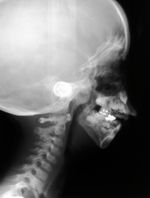

Situazione pre-operatoria

Situazione post-operatoria